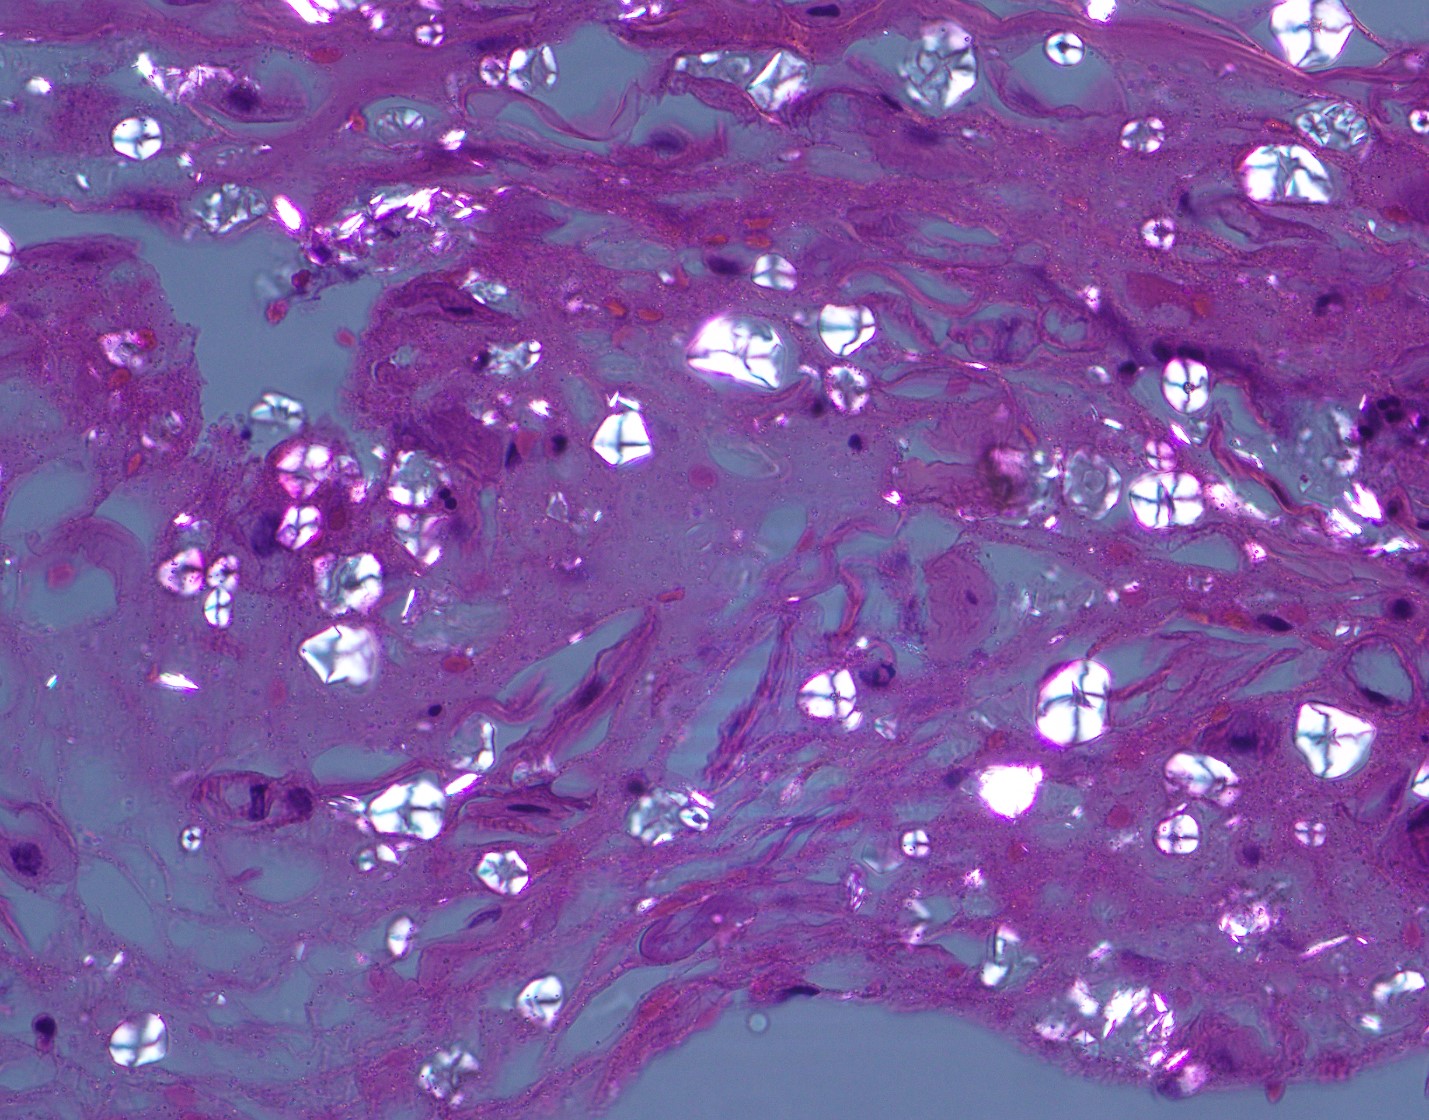

40 year old male found unresponsive. No medical or social history. The scene was unremarkable. External examination revealed scars on the forearms and legs. Autopsy revealed 450 g heart, edematous lungs, and firm liver.